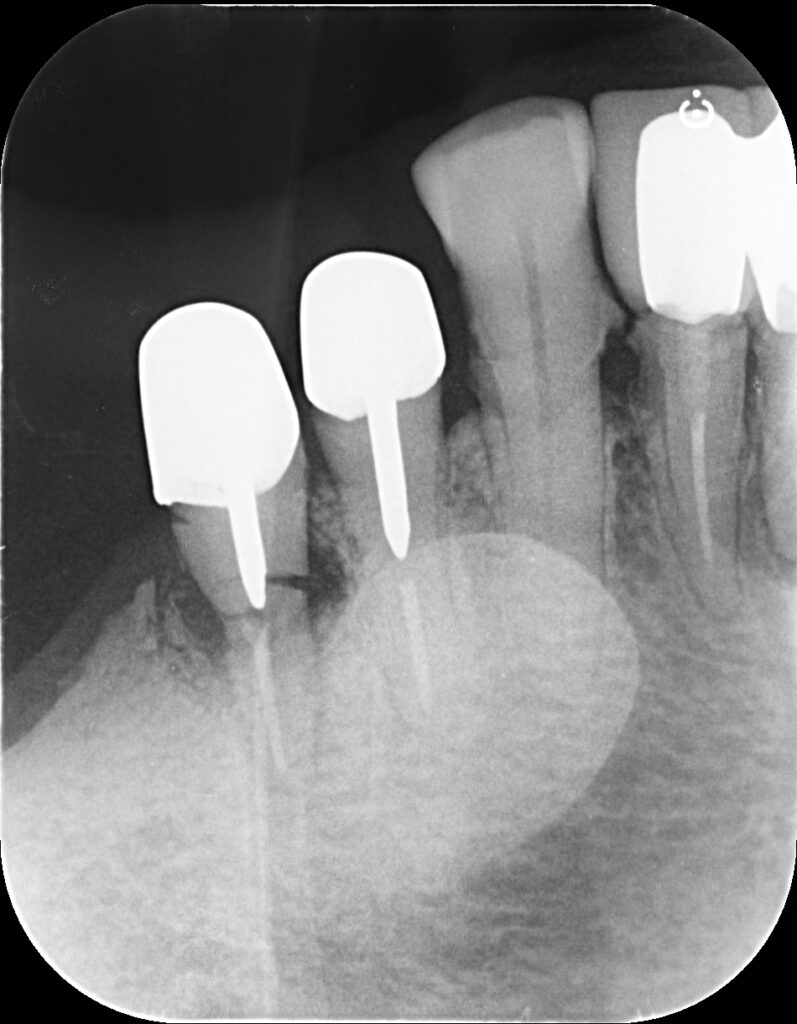

患者様のお悩みは、右下5番目の歯が割れている気がするが、かかりつけ歯科で経過観察行っているのだが改善しないので、見てほしいとのことでした。初診時レントゲン・口腔内の所見です。

【初診時】

右下5番目の歯(画面向かって一番左下の奥歯)は、レントゲン所見より真横に歯が割れているのが確認できます。残念ながら、保存は困難との診断です。